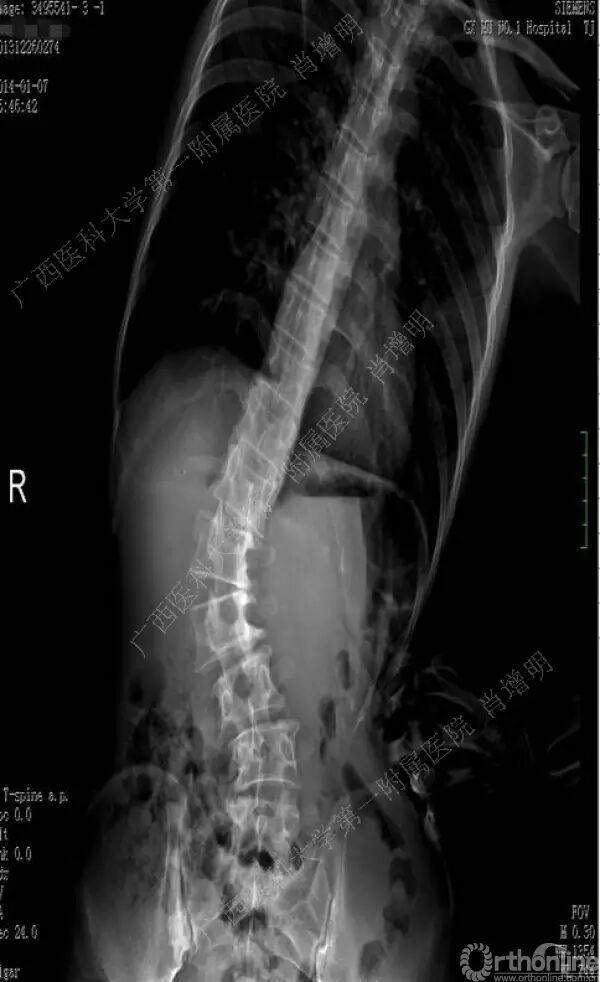

退变性脊柱侧凸是由于椎间盘退变后继发小关节退变,椎管和神经根管容积变化以及脊柱失稳,畸形等病理改变,以疼痛和神经压迫症状为主要表现的常见疾病。

退变性脊柱侧凸多发于50岁以上的中老年群体,是现代常见的老年疾病。多年来,针对该病的临床研究一直没有停步,广西医科大学第一附属医院肖增明教授细致地介绍了该病的诊疗进展。